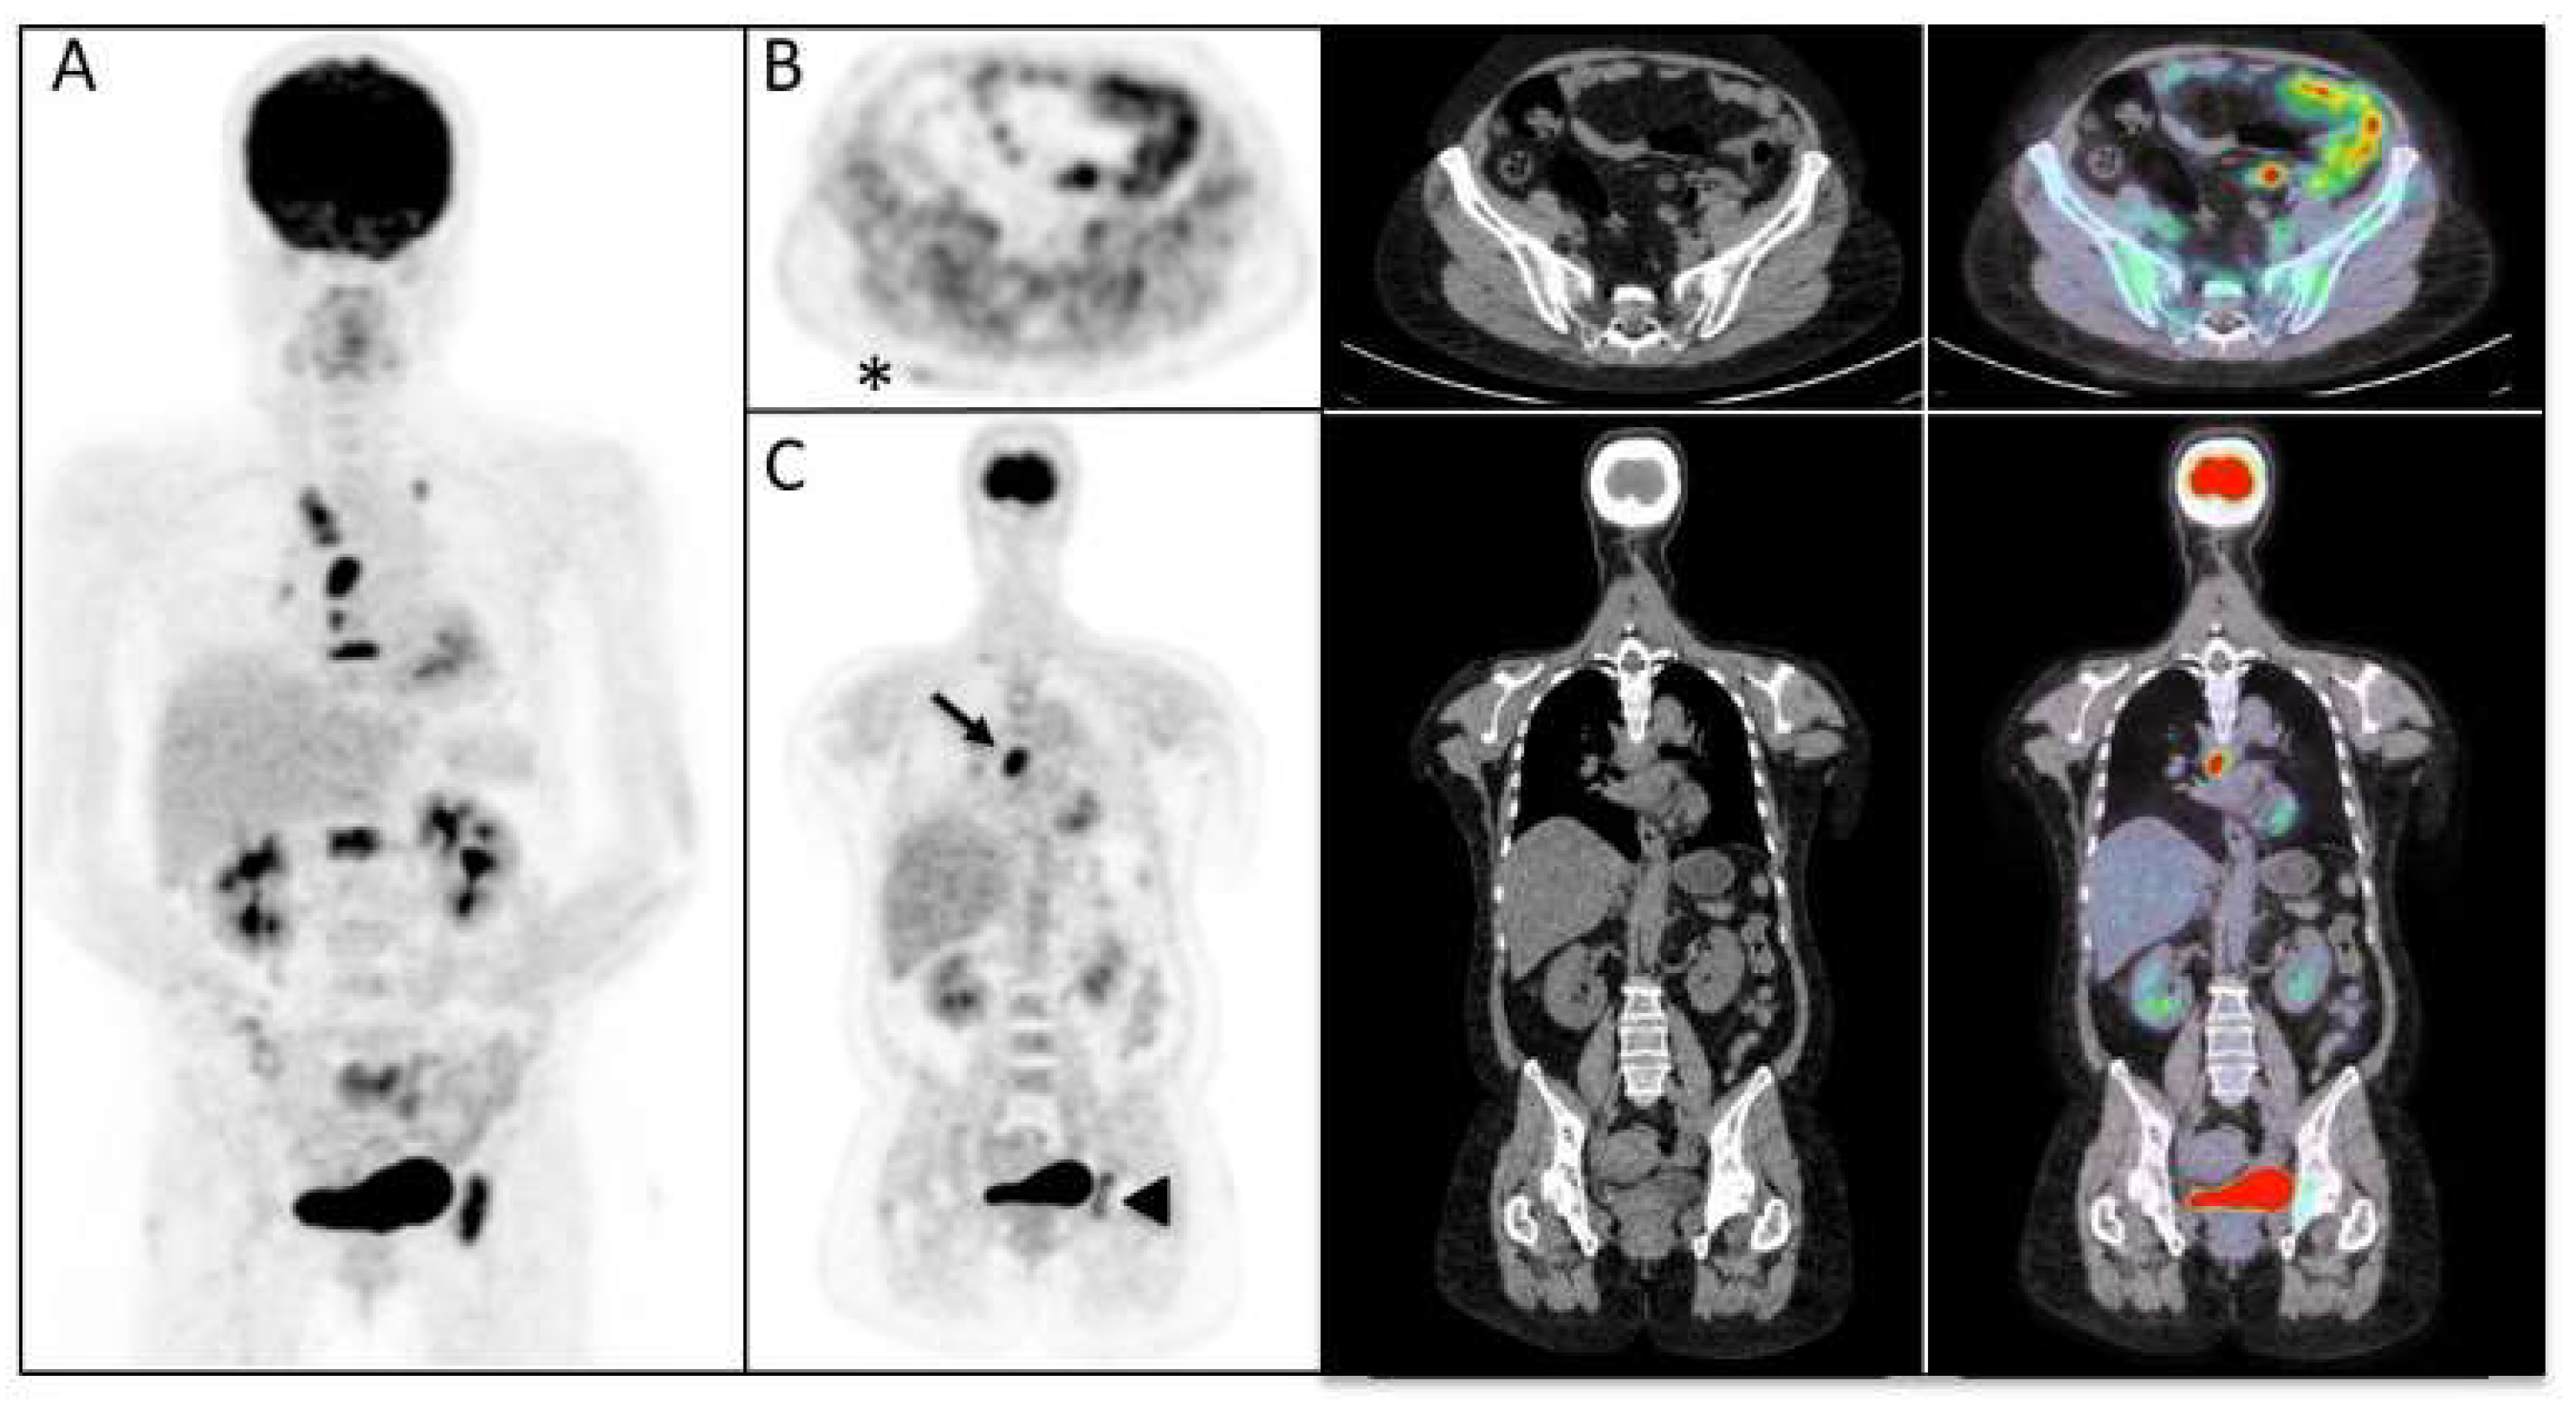

| Muscle activity on [18F]FDG-PET/CT | 13/27 (48.1%) |

| Interstitial lung diseases | 8 (27.5%) |

| Cancer detected by [18F]FDG-PET/CT | 3/27 (11.1%) |

| Dyspnea (+) | 4 | 0 | 0.002 |

| Dyspnea (−) | 3 | 20 |